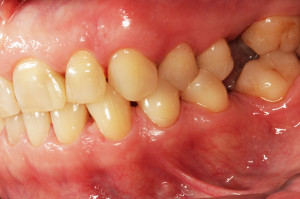

Wykonano higienizację jamy ustnej poprzez usunięcie kamienia nazębnego skalerem ultradżwiękowym, zdjęciem osadu i płytki nazębnej poprzez piaskowanie air flow plus oraz classic, a następnie wypolerowaniu gumką ze specjalistyczną pastą polerską: